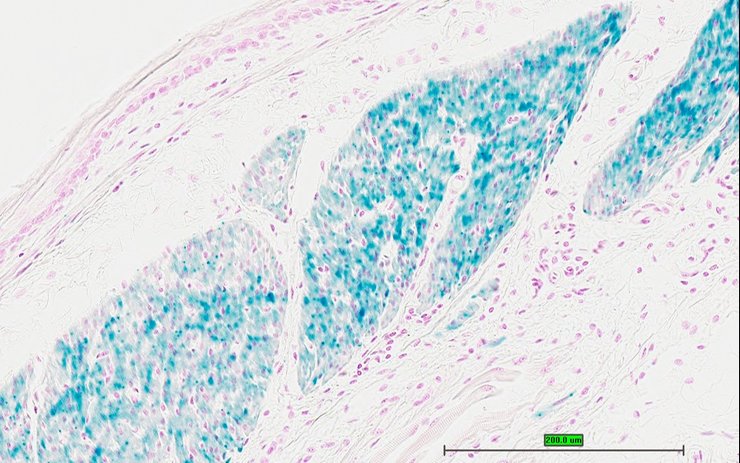

Specimen UC Davis_1879030: postnatal adult; Pmchtm1.1(KOMP)Vlcg/Pmch+ (more )

Structure Level Pattern Image Note

TS28: stomach Present UC Davis_1879030